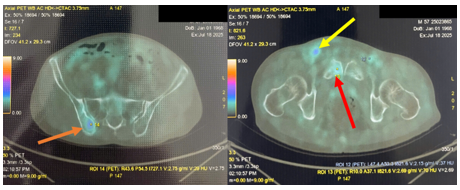

3. Hình ảnh tăng chuyển hóa FDG ở amidam bên phải (SUVmax: 3.71) Đối chiếu với nội soi.

Hình 2. Hình ảnh tăng chuyển hóa FDG ở amidam bên phải với SUVmax: 3.71 (được ký hiệu bằng mũi tên màu da cam, hình trên). Tuy nhiên, khi đối chiếu với hình ảnh nội soi tai mũi họng lại không có tổn thương nghi ngờ ác tính (Hình dưới).

Hình 4. Hình ảnh tổn thương xương chậu phải (mũi tên màu da cam), xương mu phải (mùi tên màu vàng), tăng chuyển hóa FDG khả năng ác tính (SUVmax: 3.08);hạch bẹn 2 bên tăng chuyển hóa FDG, với tổn thương có kích thước lớn và tăng bắt FDG rõ rệt ở hạch bẹn phải (mũi tên vàng), SUVmax: 4,66.

Hình 6. Hình ảnh nội soi tai mũi họng chưa phát hiện tổn thương nghi ngờ ác tính (Tai Phải: Ống tai ngoài có mảng trắng dạng nấm, Màng nhĩ dày đục; Tai trái: Màng nhĩ dày đục; Mũi: Khe sàn mũi sạch, cuốn mũi 2 bên bình thường; Vòm họng: Nhẵn, sạch, cân đối; Họng: Sạch; Thanh quản: Dây thanh 2 bên nhẵn, di động bình thường.) Mặc dù đối chiếu với PET/CT có tổn thương tăng bắt FDG tại amidan bên phải (SUVmax:3.71)

Kết quả PET/CT toàn thân của bệnh nhân tuy không phát hiện được tổn thương nguyên phát, nhưng phát hiện được rất nhiều các tổn thương di căn hạch trong ổ bụng-tiểu khung như nhiều hạch cạnh động mạch chủ, hạch dọc bó mạch chậu 2 bênvới kích thước lớn và SUVmax cao, ngoài ra còn có xương đốt sống, cánh chậu, và gan. Với những thông tin có được từ PET/CT, bác sĩ lâm sàng có thể lựa chọn các vị trí khác nhau để sinh thiết lại tổn thương tìm nguồn gốc u (ví dụ: xương,gan). Đồng thời cũng đặt ra cân nhắc về nội soi tai mũi họng lần thứ hai để khẳng định lại tính chất của tổn thương amidan phải phát hiện trên PET/CT nhưng chưa nhìn được trong nội soi tai mũi họng lần đầu tiên.